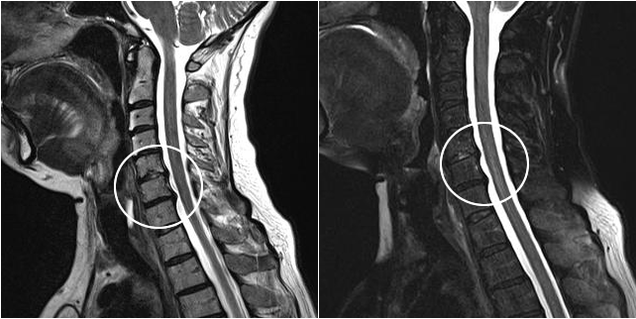

Съвременните диагностични методи включват MRI и CT, които позволяват най-точно да се изследват процесите на разрушаване на хрущялната и костната тъкан. Също така, с помощта на тази техника е удобно да се диагностицират хернии и други дефекти на меките тъкани в близост до източника на заболяването.